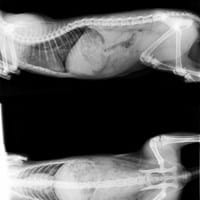

Esta es la radiografía de la patita de mi gato, ¿Operar o escayolar?